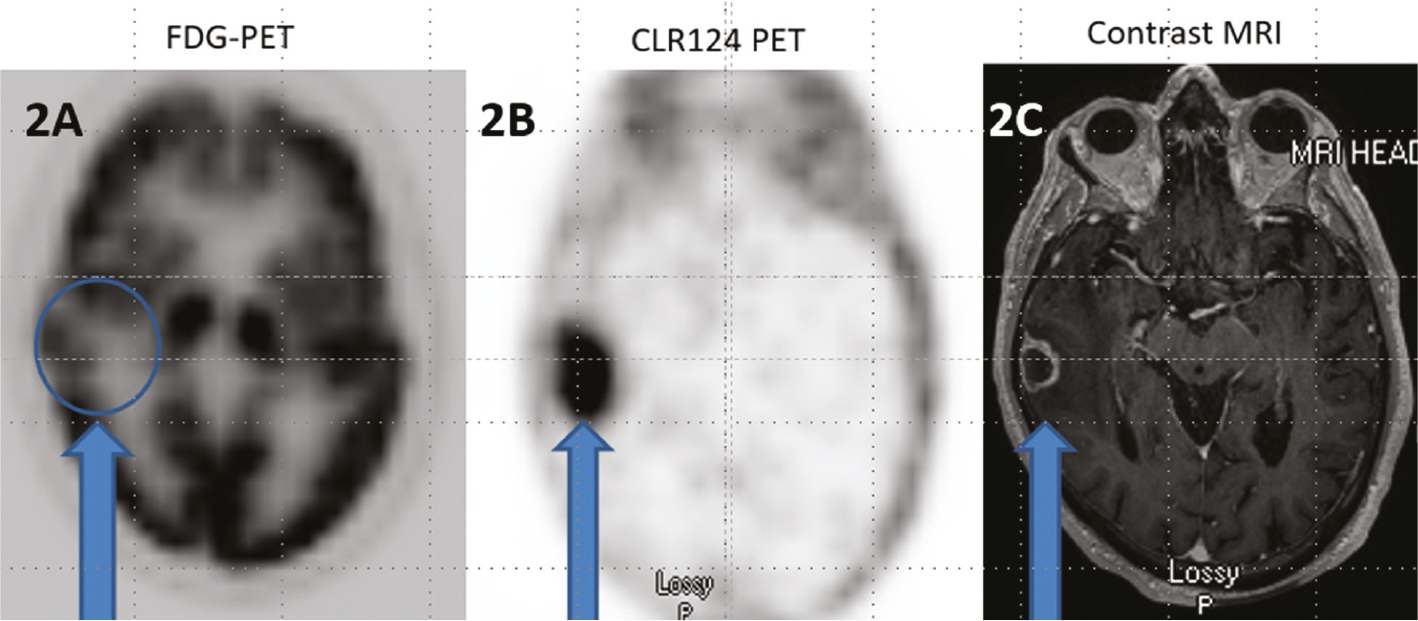

Fig 2

Figure 2. Axial 18F-FDG PET (2A), axial CLR124 PET (2B), and axial T1 contrast enhanced MRI (2C) in the same patient with a right temporal brain metastasis from non-small cell lung carcinoma. Note the high background cerebral uptake of FDG limits identification of the metastasis on 18F-FDG PET whereas the high tumor uptake compared to low background cerebral uptake of CLR124 facilitates easy identification of the metastatic lesion. The lesion is demarcated by arrows on all images and demonstrates enhancement on MRI.